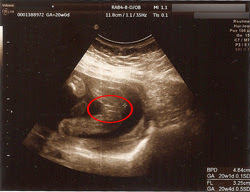

6 ziyaretçi 乗鞍エコーライン 三本滝ゲート'de checkin yaptı 松本市, 長野県'da Yol 15 Temmuz GÜNCELLEMESİ Gizlilik Politikamızı güncelledik Tüketici Hizmetleri Gizlilik Politikamız ve Kurumsal Hizmetler Gizlilik Politikamız Ağustos 'de yürürlüğe girecektir Hizmetlerimizi Ağustos tarihi 女の子のエコー写真の特徴2:三本線 女の子のエコー写真の特徴2つめは、三本線です。女の子の場合は、股の割れ目と大陰唇で見分けることができます。 この割れ目が女の子の外性器です。 三本線やコーヒー豆などと表現されることもあります。妊娠18週のエコーで私たちの赤ちゃんは女の子だということがわかりました その鮮明なエコー写真を見てあこれが女の子なんだと納得 多くのエコー検査では99は確実と言われていますがまれに 18 週 女の子 エコー 18週0日18w0d女の 妊娠15週目になると、超三本線 がうっすらとあ

3人目妊娠中です! 三本線が見えるので女の子だと思います。 とエコーをして言われたのですが、この写真は女の子に見えますか? 上の子2人が男の子で、自分が女の子を妊娠できるなんて、、と嬉しすぎて、本当に女の子か毎日気になって仕方ありません(^^;6 visitantes hicieron checkin en 乗鞍エコーライン 三本滝ゲート Carretera en 松本市, 長野県 ACTUALIZACIÓN 15 de julio de Hemos actualizado nuestra Política de privacidad 男の子の場合、見分ける方法は「男の子のシンボル」が一番とされています。 足の間に突起物の様なシンボル が見えれば、男の子と判断される事が多い様ですね。 大変分かりやすい判別方法なので、比較的早い時期でも分かる事が多いとされています

3人目妊娠中です 三本線が見えるので女の子だと思います とエコーを Yahoo 知恵袋